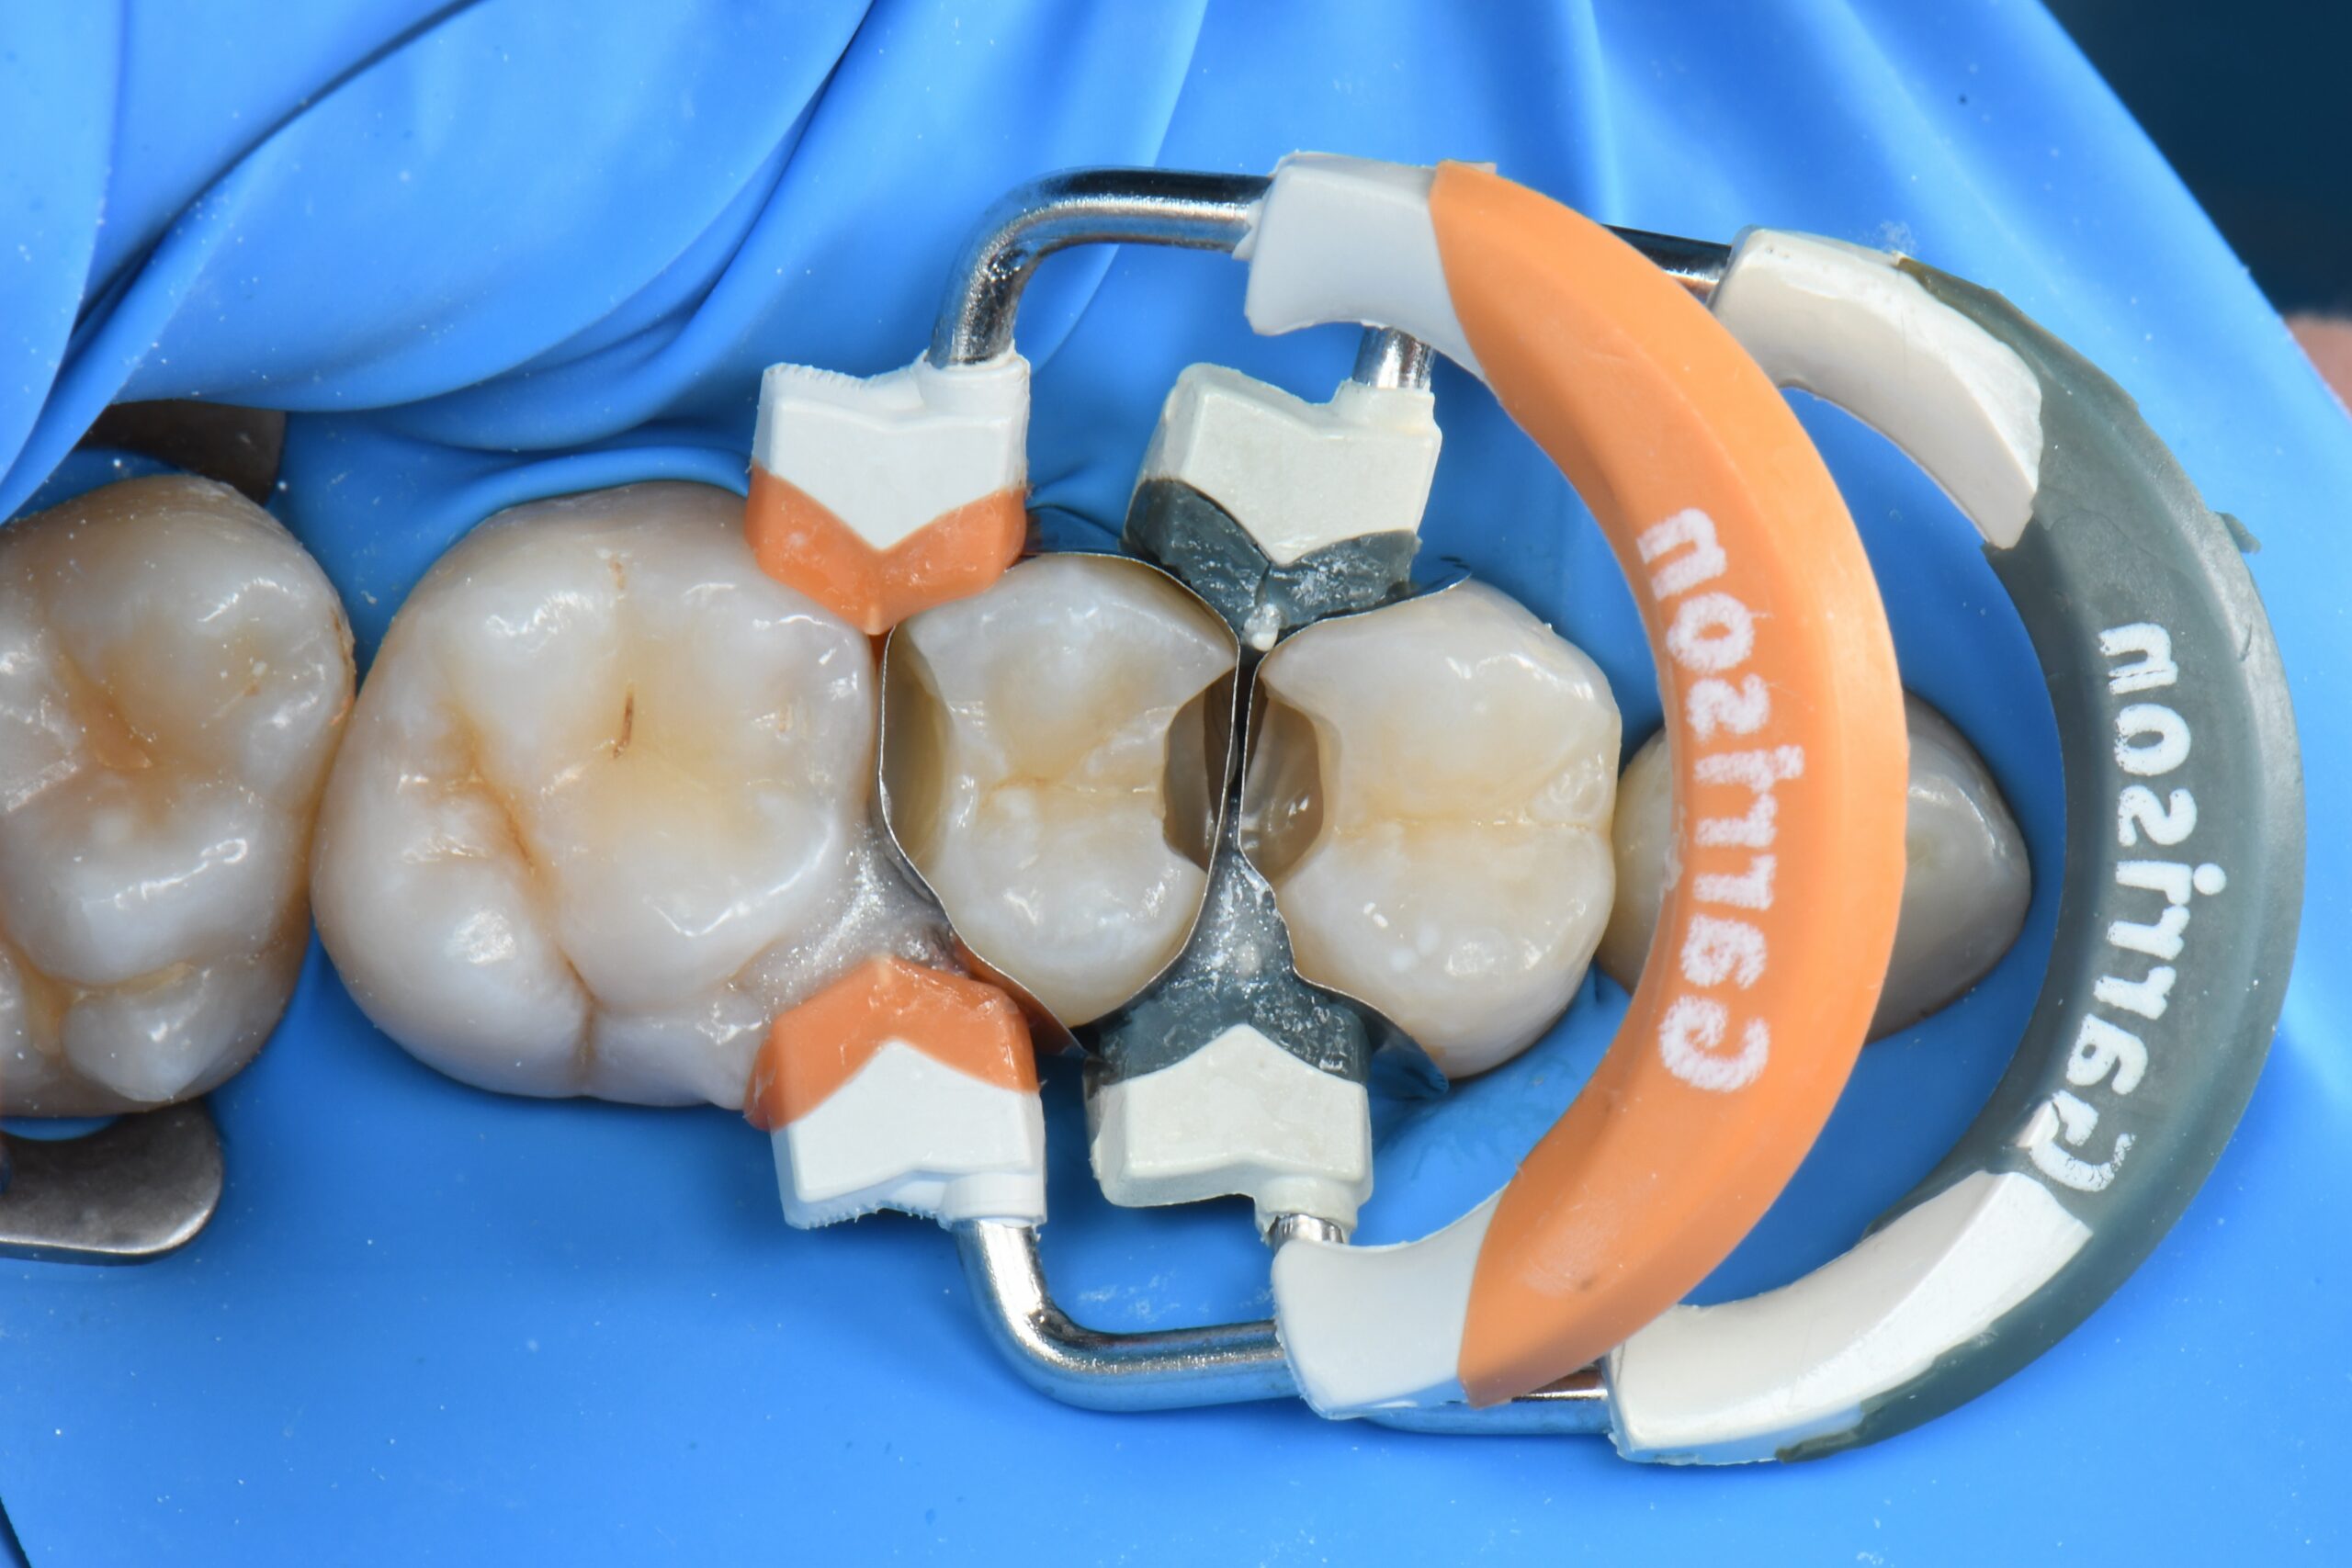

Close-up of molar teeth with dental matrix bands and wedges in place for restorative treatment

Sectional matrices, wedges and rings are properly placed, and selective enamel etching is performed.